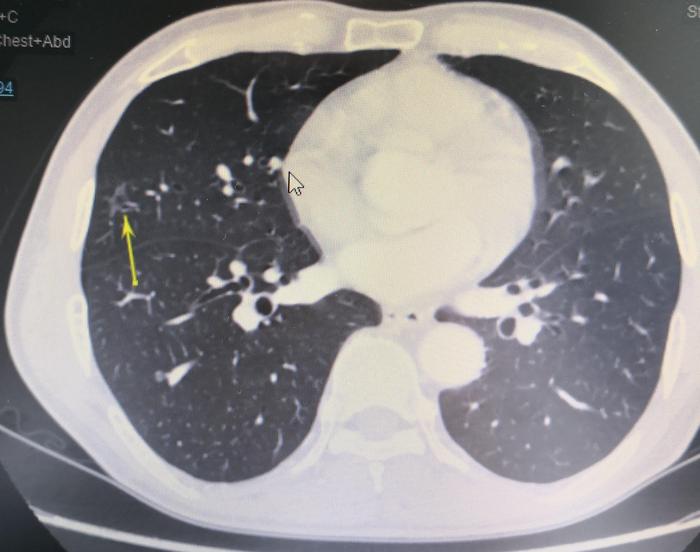

下图(图2),黄色箭头指示的是右中肺磨玻璃结节。这张CT位于上一张CT的足侧1mm。

下图(图3),黄色箭头指示的是右中肺磨玻璃结节。这张CT位于上一张CT的足侧1mm。

上图(图3),右中肺磨玻璃结节中还可以看到小空泡。病变性质倾向于肺癌。